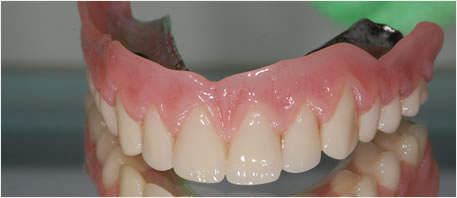

Denture Secured With Dental Implant

dental implants northern ireland